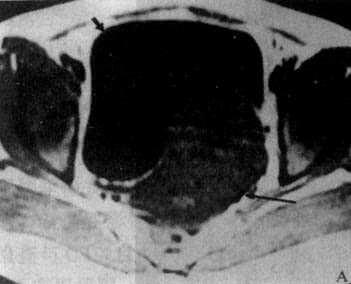

(一)子宫肌瘤CT表现为子宫增大,有时可见肿块向外隆突或呈分叶状。肌瘤密度可等于或低于正常子宫。如出现瘤内钙化则可确诊为子宫肌瘤。子宫肌瘤在T1WI上表现为均匀的中等强度信号,略低于正常子宫肌层,但难以区分;T2WI上则肌瘤信号高于子宫肌层,易于识别。瘤内钙化表现为低信号。坏死区在T1WI上为低信号,T2WI上为高信号(图4-5-7)。

图4-5-7 子宫肌瘤MRI

T1WI横切面,子宫肌瘤表现为中等强度信号,轮廓光滑整齐(↓),压迫膀胱左后壁(↓)

B、T2WI子宫肌瘤信号稍低且不均匀(↓),膀胱内尿液成为极强信号(↓)